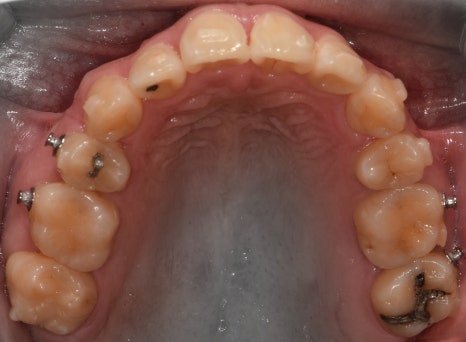

『발치 및 장치 부착, 인비절라인 진행』

표시를 해 둔, 갈고리처럼 생긴 것들은

Power arm 이라는 것들입니다.

이는, 치아들을 계획 했던 대로 정확히

이동을 시키게끔하는 보조수단으로 쓰입니다.

이후, 발치 공간이 조금씩 거의 다 폐쇄되면서

인비절라인 실버버튼을 부착시킵니다.

이것 또한, 보조도구입니다.

치열 전체를 덮는 인비절라인과 같이 맞물려서

정확한 치아의 위치 이동을 돕는 역할입니다.